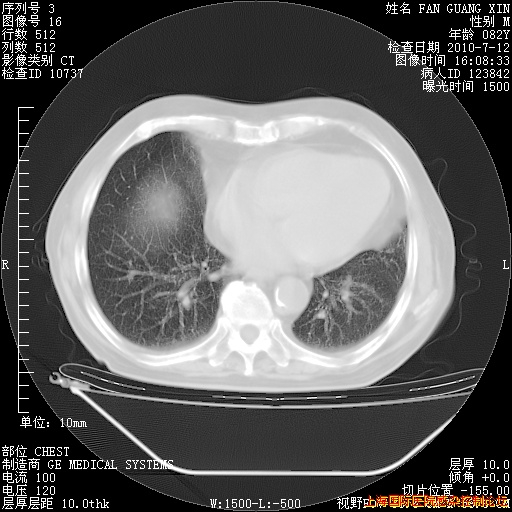

今天复查CT

今天CT

整整相隔30天的肺部CT好像有所好转啊。甲强龙减量第3天,需要观察体温。

海管,自昨日你和我通完话后,不知您岳父消化道症状有无缓解?体温怎样?阅读7.12日胸部ct,个人认为目前激素治疗是有效的,甲强龙减量是适宜的。因在抗痨治疗,需密切观察肝功、肾功能和血常规。不过,老年、长期住院和大量使用激素,很担心菌群失调发生